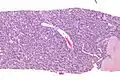

Micrograph of an adenomyoepithelioma. H&E stain. | |

An adenomyoepithelioma of the breast is a rare tumour in the breast composed of glandular elements (adeno-) and myoepithelial cells. It is usually benign;[1] however, there are reports of malignant behaviour.[2]

The histomorphologic appearance can mimic invasive ductal carcinoma, the most common type of invasive breast cancer.